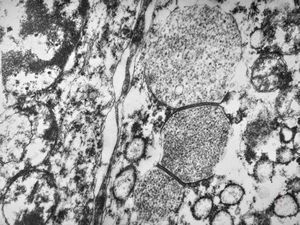

M,2y. | dense mitochondrial inclusions - clinically susp. Zellweger syndrome